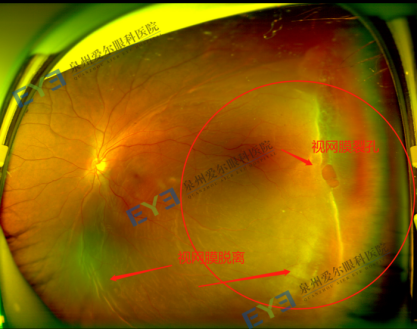

(视网膜脱离眼底照片)